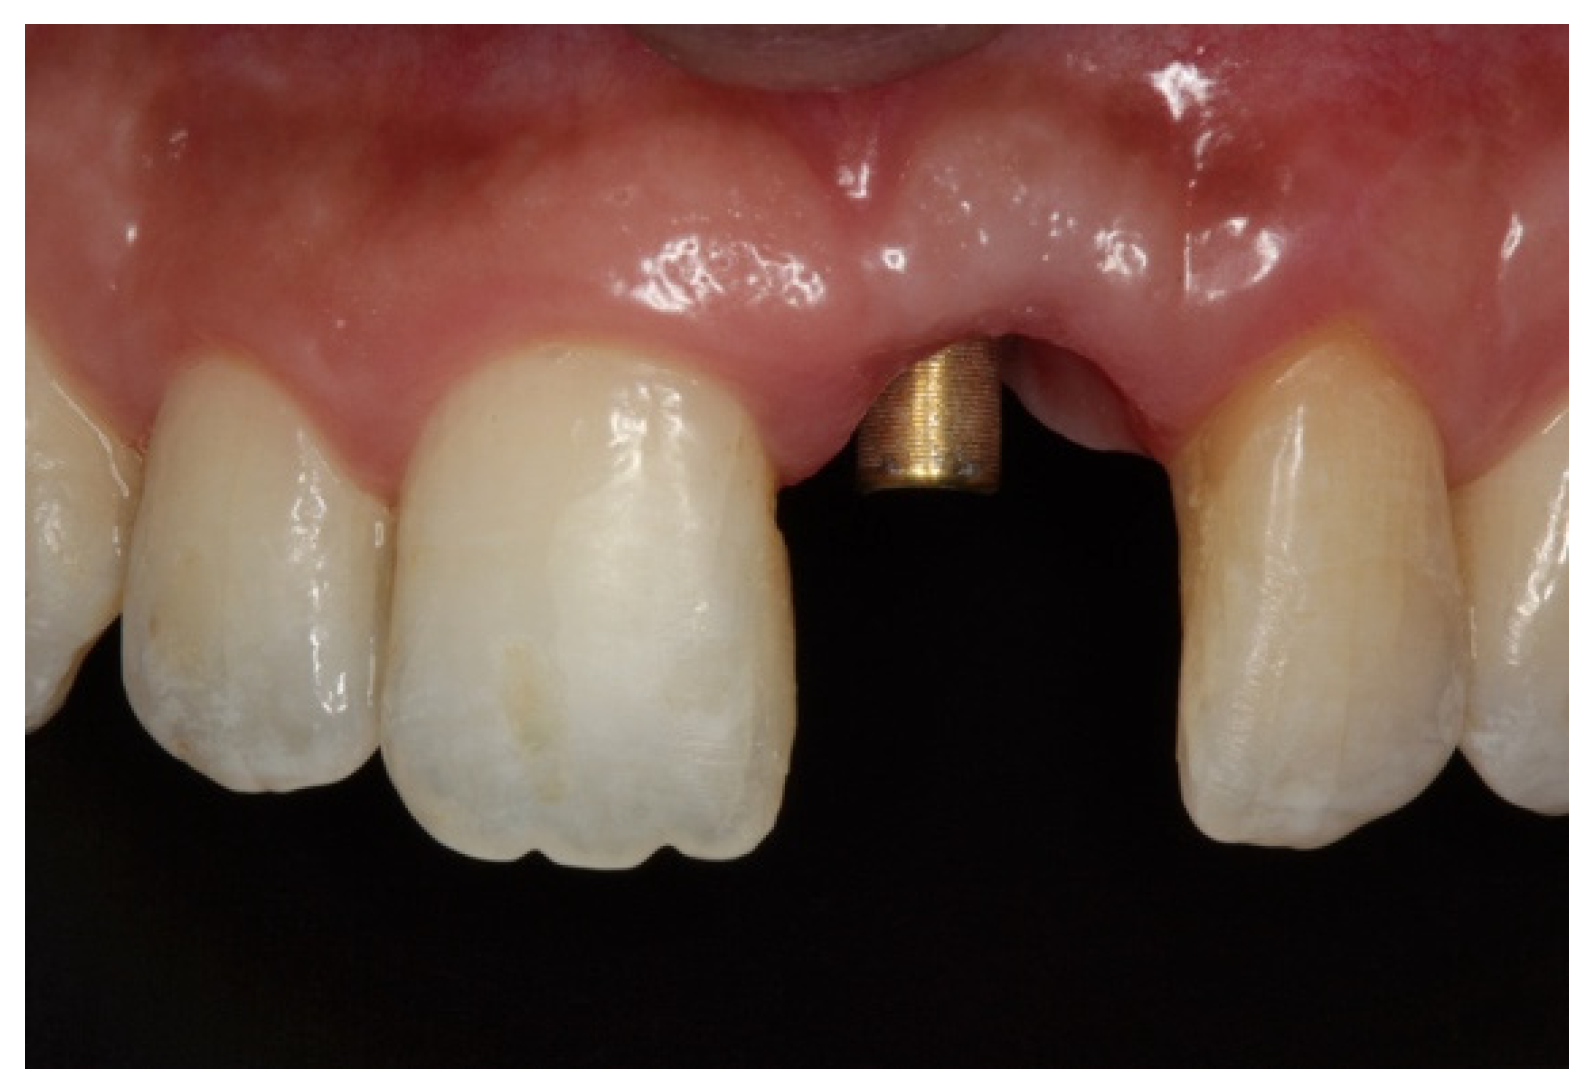

On clinical inspection of the aesthetic area, it was observed in all patients that the integrity of the vestibular plate was compromised by significant physiological and structural changes after extraction (Figure 1). This was verified through periapical radiographs and/or panoramic and dental CBCT, which provided sagittal and frontal slices for analysis. On sagittal CBCT images, the anteroposterior distance of the CNP at the level of its upper, middle, and lower thirds was calculated. Axial plane images were in turn used to determine NPC height from the level of the upper bifurcation to the palatal opening, and the width of the residual crest in the toothless zone [24,25].

Figure 1.

(A,B) Initial presentation of a patient wearing a removable partial prosthesis replacing a missing left upper central incisor.

Implants were activated 6 to 10 months after placement. A temporary acrylic crown was screwed to the implant, and a temporary resin abutment (Peek® BioHorizons, Birmingham, AL, USA) was used to shape the cervical contour and emergence profile (Figure 6).

Figure 6.

(A) Initial provisionalization (adhesive bridge). (B) Subsequent customized provisionalization, screwed down to create the emergence profile.